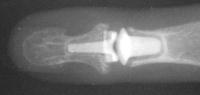

Clinical Example: Distal Interphalangeal Joint Arthroplasty with reversed Ascension carbon implant arthroplasty

These two cases illustrate the use of the Ascension PIP joint implant arthroplasty in the DIP joint position. The stem of the distal component is too wide to fit into the typical distal phalanx, but the proximal component stem will, and in selected cases, the implant will fit in this position if it is placed in a reversed proximal-distal position. These cases illustrate this technique - not as an endorsement, but as a demonstration of  technical feasibility. At one year, each  reconstructed joint was painless and had about 30 degrees range of motion.

Final implant radiographs.